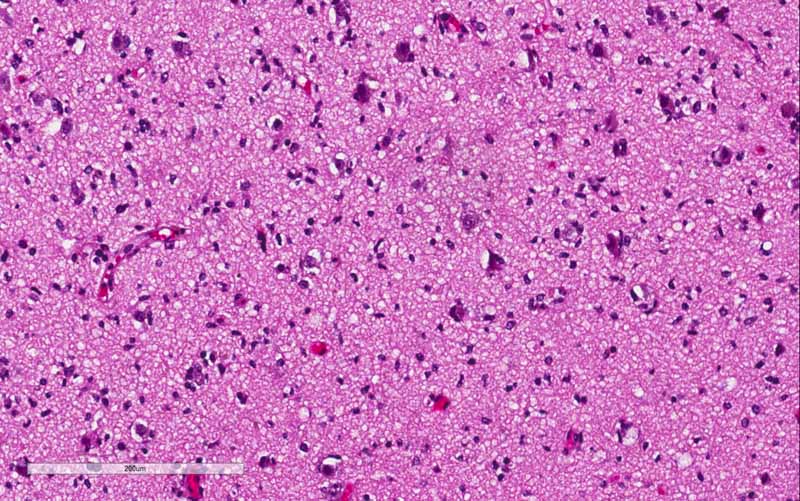

Pathology of the Case: The tumor seems to have a biphasic pattern. In some of the areas, it has the classic features of a neoplastic glial neoplasm (Panel C, D,, & E). These areas show a rather homogenous proliferation of neoplastic glial cells with high-grade nuclei. Note the spongiotic background (Panel E) and this probably are the edematous area demonstrated on FLAIR. In the remaining parts of the specimen, however, there are islands of large, bizarre cells that are well-demarcated (Panel F) from the surrounding tumor with features in Panel C and D. These large cells are characterized by a large variation in size with many of them a centrally located inclusion (Arrow in Panel G) that seems to have pushed the nucelus to an eccentric location. While some of them are binucleated (Arrow in Panel G), multinucleated tumor cells are not common. The nuclei are enlarged, pleomorphic, and with large and eosinophilic nucleoli. These cells are rhabdoid cells. Endothelial proliferation is also present (Arrow in Panel F). There is some necrosis (not shown). On immunohistochemistry, the tumor cells are negative for IDH1-R132H consistent with no mutation. The tumor cells are strongly positive for ATRX consistent with wild-type ATRX. Only occasional tumor cells are positive for p53 indicating no mutation in p53. The Ki67 labeling is much higher, up to about 30%, in the rhabdoid area in comparison to the areas with features of classic high-grade glioma (Panel H & I).

Comment on pathology: The rhabdoid area is well-demarcated fromt he surrounding high-grade glioma with a pushing margin. This phenomenon is most consistent with a high-grade/rhabdoid transfromation arising from the surrounding high-grade glioma areas. This kind of well-demarcated high-grade changes is more commonly seen in malignant/high-grade transformation in sarcomas.

Next generation sequencing panel study and chromosome microarray study were performed in this case with a block containing the rhabdoid changes. There was no loss of SMARCB1(INI1) or SMAECA4(BRG1) were demonstrated by next generation sequencing. Chromosomal changes included gain of chromosome 7, EGFR amplification, CDKN2A/B homozygous deletion, and heterozygous loss of chromosome 10. There was also mutation of TERT promoter. These features were classic for a glioblastoma. The rhabdoid changes stood out distinctly in a background of high-grade glioma.  The significant increase in Ki67 labeling in the rhabdoid area. Both features supported that the rhabdoid component was a high-grade transformation arising from the existing glioma. With all of these features taken into consideration, this is a case of glioblastoma with rhabdoid changes.